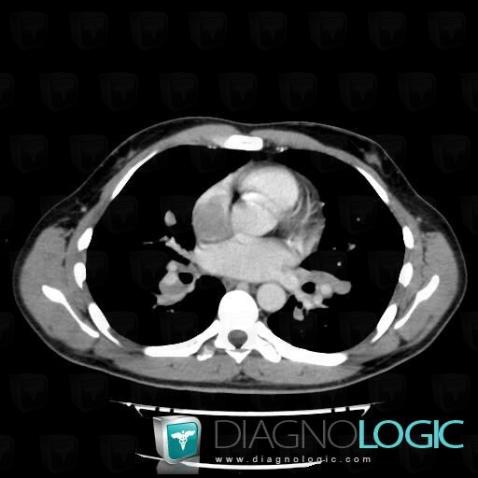

Voici les informations spécifiques à l'image clé ci dessus:

Voici les informations spécifiques à l'image clé ci dessus:

- Diagnostic Lymphome , Localisation(s) Médiastin, comportant les gammes Masse médiastinale de faible densité, Masse médiastinale moyenne